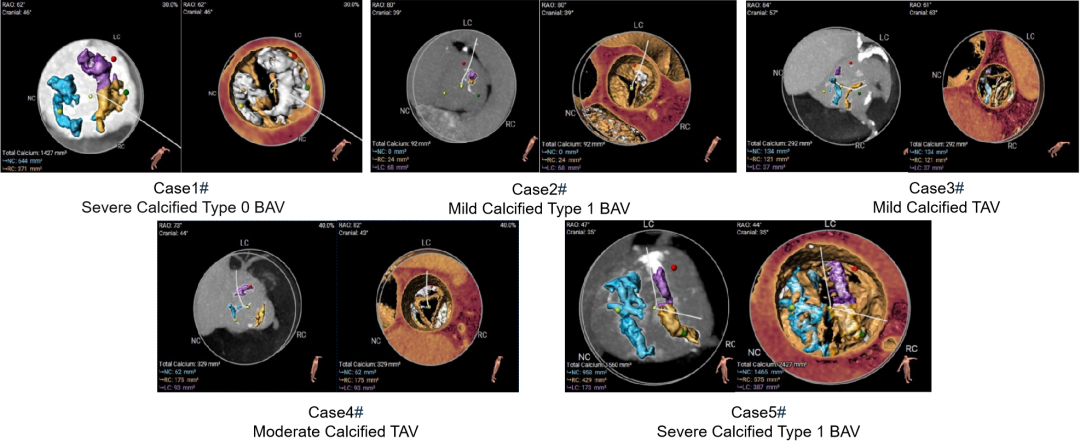

术后即刻造影

该临床试验结果已初步展示出该系统的稳定性和优异性能。5例病例涵盖了常见的各种解剖类型,包含2例Type 1型二叶瓣,1例Type 0型二叶瓣,2例不同钙化程度的三叶瓣,钙化积分最低的仅92,最高的HU850积分达到了1560,涵盖了不同手术难度和解剖类型的病变。这些持续的临床结果为未来机器人辅助TAVR手术的可行性和安全性提供了坚实的证据。